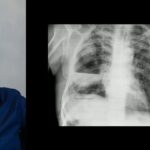

Análise de uma Radiografia de Tórax: Abscesso Pulmonar

Olá! Sou o Dr. João, médico radiologista, e estou aqui para ajudá-lo a interpretar uma radiografia de tórax que você possui. Antes de analisar a radiografia, é importante lembrar que a interpretação deve ser feita sempre dentro de um contexto clínico. Portanto, é essencial conhecer o motivo pelo qual o exame foi solicitado. No caso de um paciente com febre, tosse e falta de ar, as primeiras hipóteses que geralmente consideramos são relacionadas a uma infecção do trato respiratório, especialmente do trato respiratório inferior, como os pulmões.

Ao analisar a radiografia, podemos observar algumas opacidades difusas no pulmão, apresentando características de opacidades algodonosas ou consolidações. Essas opacidades podem parecer amontoados de algodão ou até mesmo pontos e linhas irregulares. Esse padrão é conhecido como infiltrado reticulonodular, e não é específico para identificar um vírus ou uma pneumonia. É apenas uma forma de descrever o pulmão com uma aparência “sujinha”. Além disso, também podemos observar um padrão broncopneumônico, o que sugere uma infecção mais grave e mais difusa nos pulmões.

Contudo, o achado mais relevante nessa radiografia é a presença de um grande abscesso pulmonar na projeção do terço médio do pulmão direito. Ressalto que estamos trabalhando em uma radiografia frontal, portanto, não temos a visualização do perfil para localização precisa da lesão. O ideal seria ter uma radiografia em perfil para determinar com mais precisão a localização. No entanto, considerando a descrição, podemos afirmar que o abscesso está presente no terço médio do pulmão direito.